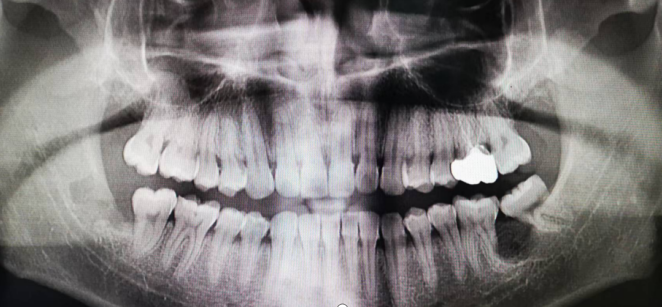

下面提供一例我们日常诊疗中接诊的病例:为智齿颊侧阻生,压迫邻牙牙槽骨吸收,引起邻牙松动,现已拔除阻生智齿,囊肿开窗减压,定期复查囊腔逐渐缩小,新骨逐渐形成,愈合良好。

左下第三磨牙颊侧阻生